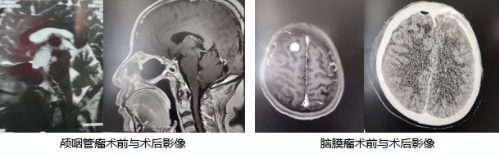

面对颅咽管瘤深藏于鞍区这一“生命禁区”的险境,传统手术往往需要大开颅手术,集团本部神经外科主任孙国庆综合考虑后,选择了经鼻腔神经内镜这种微创手术方式,通过神经内镜这把精密的“钥匙”,纤细的内镜如灵巧的手指,经由鼻腔自然通道探入大脑深处,高清视野下,肿瘤与周围脆弱的视神经、垂体、颈内动脉界限分明,凝神屏息,在内镜辅助下对肿瘤展开精准剥离,每一毫米的推进都是对生命禁区的敬畏与挑战,最终成功将这颗深藏的“定时炸弹”完整清除。

而对于位于大脑的脑膜瘤,虽然肿瘤较小,但位于运动功能辅助区,稍有不慎就会出现瘫痪的风险,孙国庆主任则切换至高倍显微镜的高清视野。显微镜下,肿瘤边界与脑组织清晰可辨,如同在微观世界展开一场精密的地形测绘。专家沿着肿瘤边界耐心分离,将供血血管逐一凝闭处理,全程保护着下方珍贵的脑功能区。显微镜如同为医生装上了“超级慧眼”,最终将这个表面威胁也干净利落地彻底移除。

经由两次手术,分别应用“神经内镜、显微镜”两套神器,一个共同目标:为生命彻底减负。神经外科专家团队丰富的经验与精准判断,让复杂手术成功化为现实。杨女士术后恢复远超预期,视力稳步回升,恼人的头痛烟消云散。重获健康的她感慨万千:“手术前那些辗转难眠的夜,是海慈的温馨医疗为我点亮了灯。这里的医生,不仅手握技术利刃,更懂得如何用心托住患者的希望。”